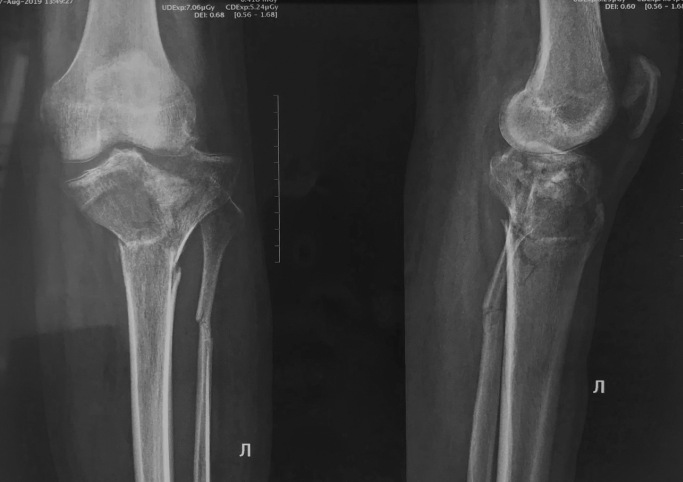

Срастающийся со смещением перелом проксимального метафиза большеберцовой кости

Обратился пациент 28 лет с переломом проксимального метафиза большеберцовой кости. Травма в мае 2019 года.

При получении травмы отказался от лечения в стационаре (убеждали всем отделением, никак), лечился в гипсовой повязке. Спустя 3,5 месяца обратился к нам.

Имеется выраженная контрактура в коленном суставe, фактически качательные движения. Кроме того, голеностопный сустав также малоподвижен, стопа фиксирована в положении подошвенного сгибания (дефект иммобилизации, гипс снят 2 недели назад).